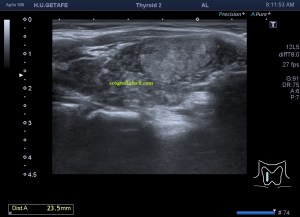

El paciente viene por un bulto en la parte derecha de la espalda, en la región paradorsal alta. Con una sonda de alta frecuencia accedo a la región, que era palpable. Lo primero que observo es que la transmisión del paciente no es buena, esto que a veces pasa que encuentras pacientes, que no sé explicar el motivo, no transmiten bien.

Me da para observar que en la zona de palpación encuentro, profundo en la imagen, un formación hiperecogénica, que está dentro de un músculo. Antes de detallar los hallazgos de la imagen lo que quise fue reconocer bien la anatomía. La piel y el tejido celular subcutánea era muy fácil, también saber que esta anatomía superficial estaba intacta y que la lesión estaba intramuscular, pero me encontraba dos planos musculares, uno superficial, el otro profundo, el profundo con la lesión.

El protocolo es el típico, cortes en eje corto y largo, con doppler, para comprobar vascularización, como línea roja del lipoma. Imágenes 3,4 y 6.

Después con la radióloga, hicimos una imágenes con «panoramic view» que te dan un detalle de las anatomía con respecto del lado contralateral, sano. Imagen 1.